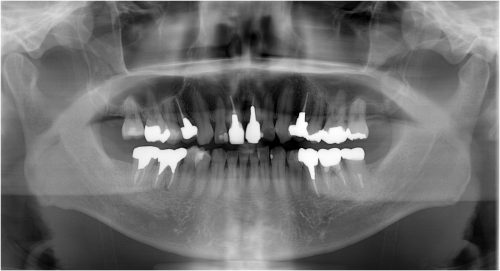

インプラント 右上4567 川口で精密インプラントなら さかえ歯科

川口で精密インプラントなら さかえ歯科クリニック